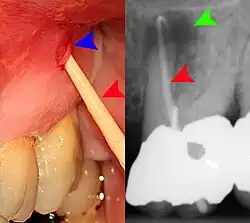

Clinical & xray correlation of pericoronitis

An operculum (green arrow) over a partially erupted lower left third molar tooth. There is minimal inflammation and recurrent swelling.

xray of pericoronitis

A radiograph of the above tooth showing chronic pericoronitis, operculum (blue arrow) and bone destruction (red arrow) from chronic inflammation. Tooth is slightly disto-angular.